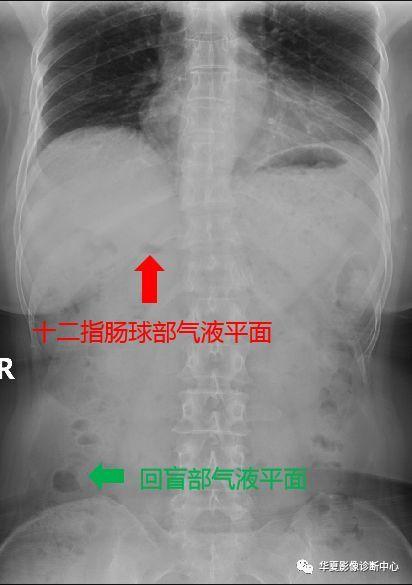

十二指肠球部(灯泡样),回肠末段及结肠胃底腹部常见的正常气-液平面

肠梗阻x线气液平面图

肠梗阻气液平面图片